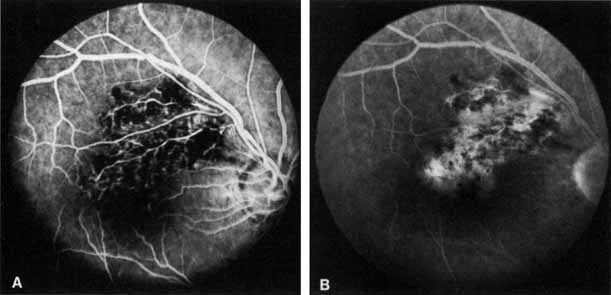

Fig. 1 A. “Blood and thunder” appearance of a central retinal vein occlusion. B. Intravenous fluorescein angiogram shows this occlusion is primarily ischemic or nonperfused. The fact that there is more nonperfusion in the inferior half of the fundus compared with the superior half is unusual.

Coats55 may have been the first to suggest that patients with central retinal vein occlusion fall into two groups: one with a dramatic, “blood and thunder” ophthalmoscopic appearance, loss of vision, and a poor prognosis (see Fig. 1); and the other with mild ophthalmoscopic changes, generally good visual acuity, and a relatively good prognosis (Fig. 2). Other investigators have commented on the difference in severity among central retinal vein occlusions, relying principally on the fluorescein angiogram to assess the severity of occlusion.56–59

Fig. 2 A. Nonischemic central retinal vein occlusion. Note venous engorgement, dot, blot, and flame-shaped hemorrhages, blurring of disc margins, and a hemorrhage overlying the macula. B. Fluorescein angiogram reveals mild venous engorgement and tortuosity with virtually no capillary nonperfusion.

Fig. 4 Fluorescein angiogram after moderately ischemic central retinal vein occlusion. A. Early venous phase. The capillary bed is dilated and engorged. Punctate areas of fluorescence represent microaneurysms or small areas of capillary leakage. B. Midvenous phase. There is considerable delay in venous return and an increase in and coalescence of punctate areas of extravascular fluorescence. C. Late venous phase. Fluorescence staining along the vein margins and scattered areas of capillary nonperfusion (arrow) are present.

Fig. 5 Fluorescein angiogram of acute ischemic retinal vein occlusion. Capillary nonperfusion is essentially 100%.